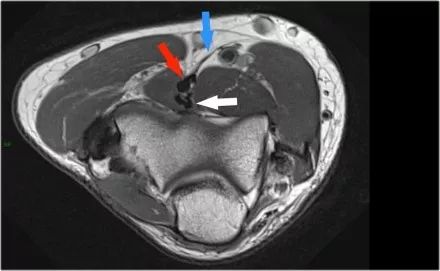

在研究韧带时,尤其是UCL,始终使用轴向图像。如果你看内侧上髁,你会发现后束是一个薄的结构(蓝色箭头)。注意在肘管内的尺神经。

后束形成肘管隧道的地板。支持带覆盖肘管。请注意,前束更厚(白色箭头)。您可以看到前韧带和后韧带之间的区别,即使它们形成一条韧带。走向远端,我们会看到它们合并在一起以附着于崇高的结节。

尺神经:在这里,我们看到了肘管内的尺神经。尺骨侧支带的后带形成隧道的底部,而支持带形成屋顶。

该患者有尺神经神经病变。肘管综合征是一种常见的周围神经病变。它产生于肘管内尺神经,其中该神经传递肘管支持带的下方的压缩。